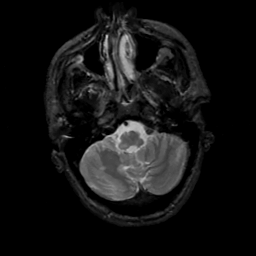

MR Study #5, March 10, 1991 -- Slice #10

[Home][Help][Clinical][Tour 1][Tour 2] Slice 10